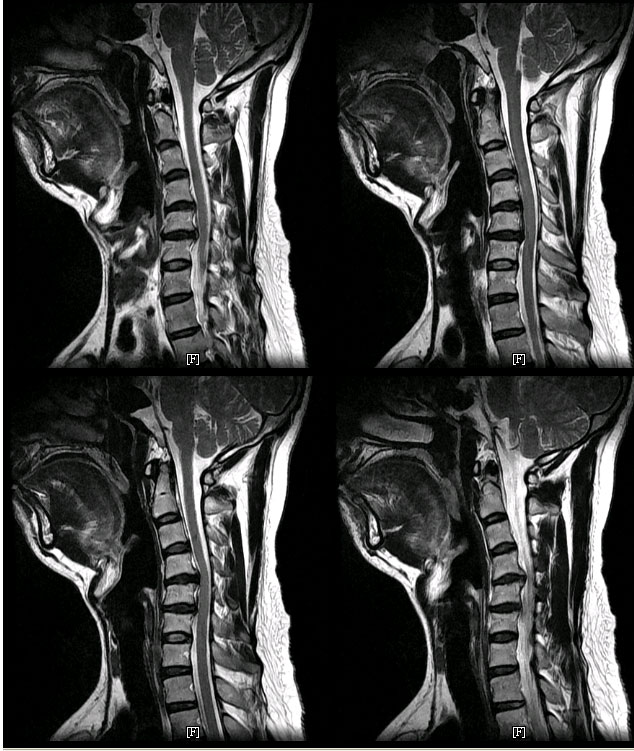

ũ 4,56,7 ũ Ƽ Űֻġ 2ȸ ϴ Ȱ mri Ϸ ϴ ּ A/S ۿ īμ Ա 2009-07-30 ݼ Ű 171 78 38 ˰Ե ͳ õ ش 1C.Ż, 1C., 2C.ھ˷⼺(˷) ḷ 6C.ڸ 6C. κ 6C.ھ Ḳ 6C.ڻ ()ũ( ߰Ż) Ը ũ(߰Ż)ġ, հ , ġ, , Ḳ ġ ϰ Ѱ ũ ġḦ Ϸ մϴ ˷ּ |